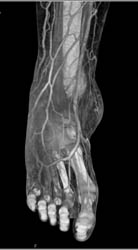

Tibial Fracture and Open Wound